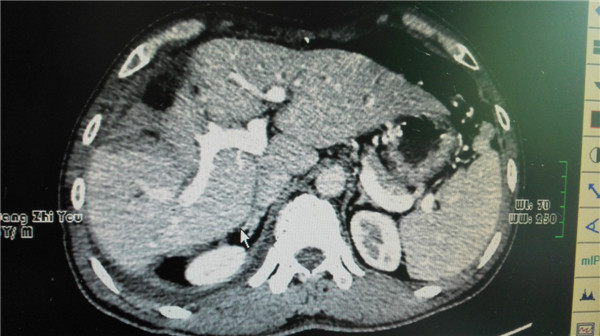

术后复查CT